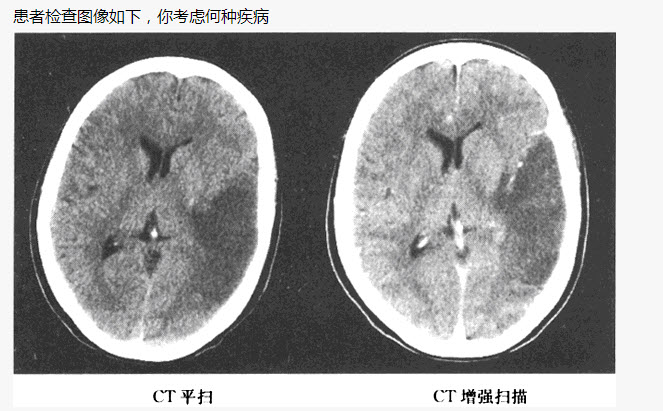

F.CT示脑实质内低密度区不强化

2、单项选择题 患者,女,80岁,被人发现昏迷,大小便失禁10小时入院。体格检查:血压180/100mmHg,心率约110次/分,有房颤,体温37℃,浅昏迷,右侧肢体未见自主活动,肌力增高,Babinski征阳性,GCS=E2+V1+M3=6分,有风湿性心脏病和房颤病史,既往超声检查有二尖瓣赘生物。

患者检查图像如下,你考虑何种疾病()

A.脑出血

B.脑梗死

C.脑动静脉畸形

D.脑膜炎

E.星形细胞瘤

F.脑膜瘤压迫静脉窦